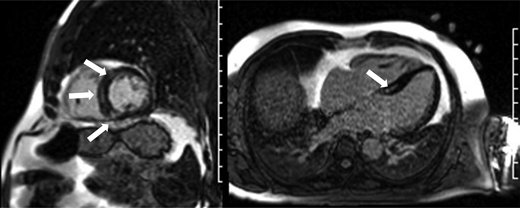

Example of cardiac magnetic resonance imaging revealing mildly reduced ejection fraction (52%; lower end of normal being 58%) with mid-myocardial delayed enhancement indicative of cardiac fibrosis (white arrows) in a long-term non-Hodgkin lymphoma survivor >30 years after doxorubicin-based chemotherapy who presented with premature ventricular contractions.